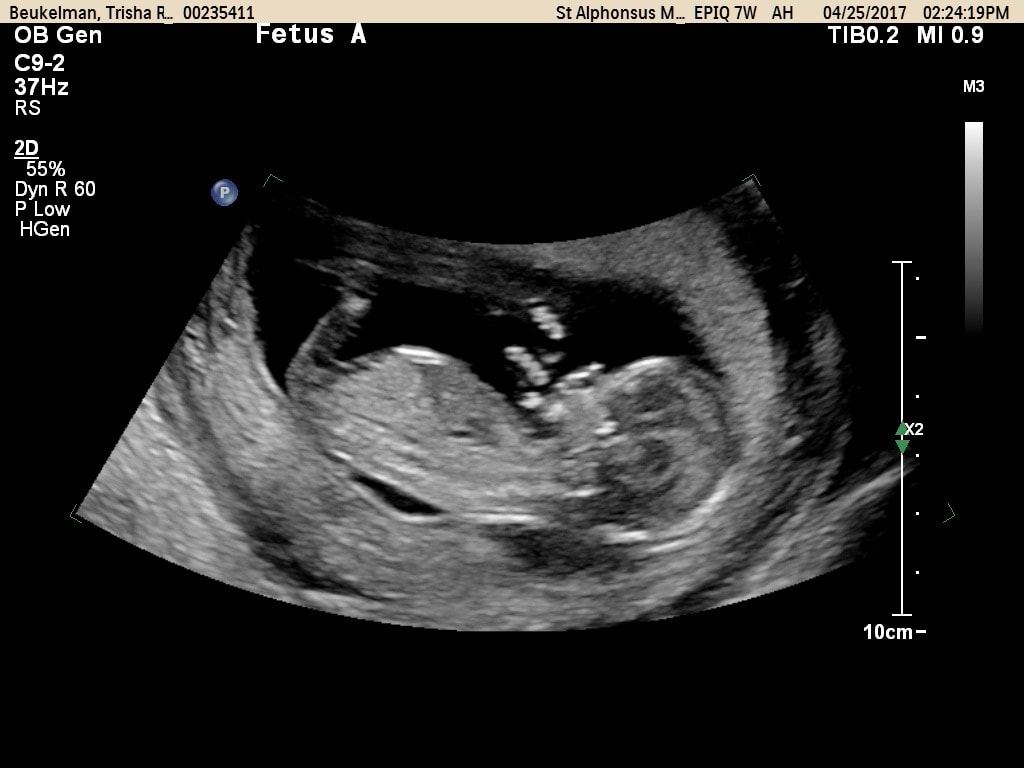

- Ultrasound Photos at 13 Weeks Pregnant With Twin

Ultrasound Photos at 13 Weeks Pregnant With Twin